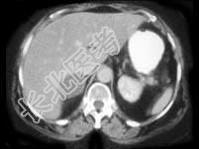

- 单项选择题女,45岁, 满月脸、向心性肥胖2年余,实验室检查: 血、尿皮质醇增高,结合CT图像, 最可能的诊断是 ( )

A、右肾上腺腺瘤

B、右肾上腺腺癌

C、右肾上腺转移癌

D、左肾上腺嗜铬细胞瘤

E、左肾上腺增生